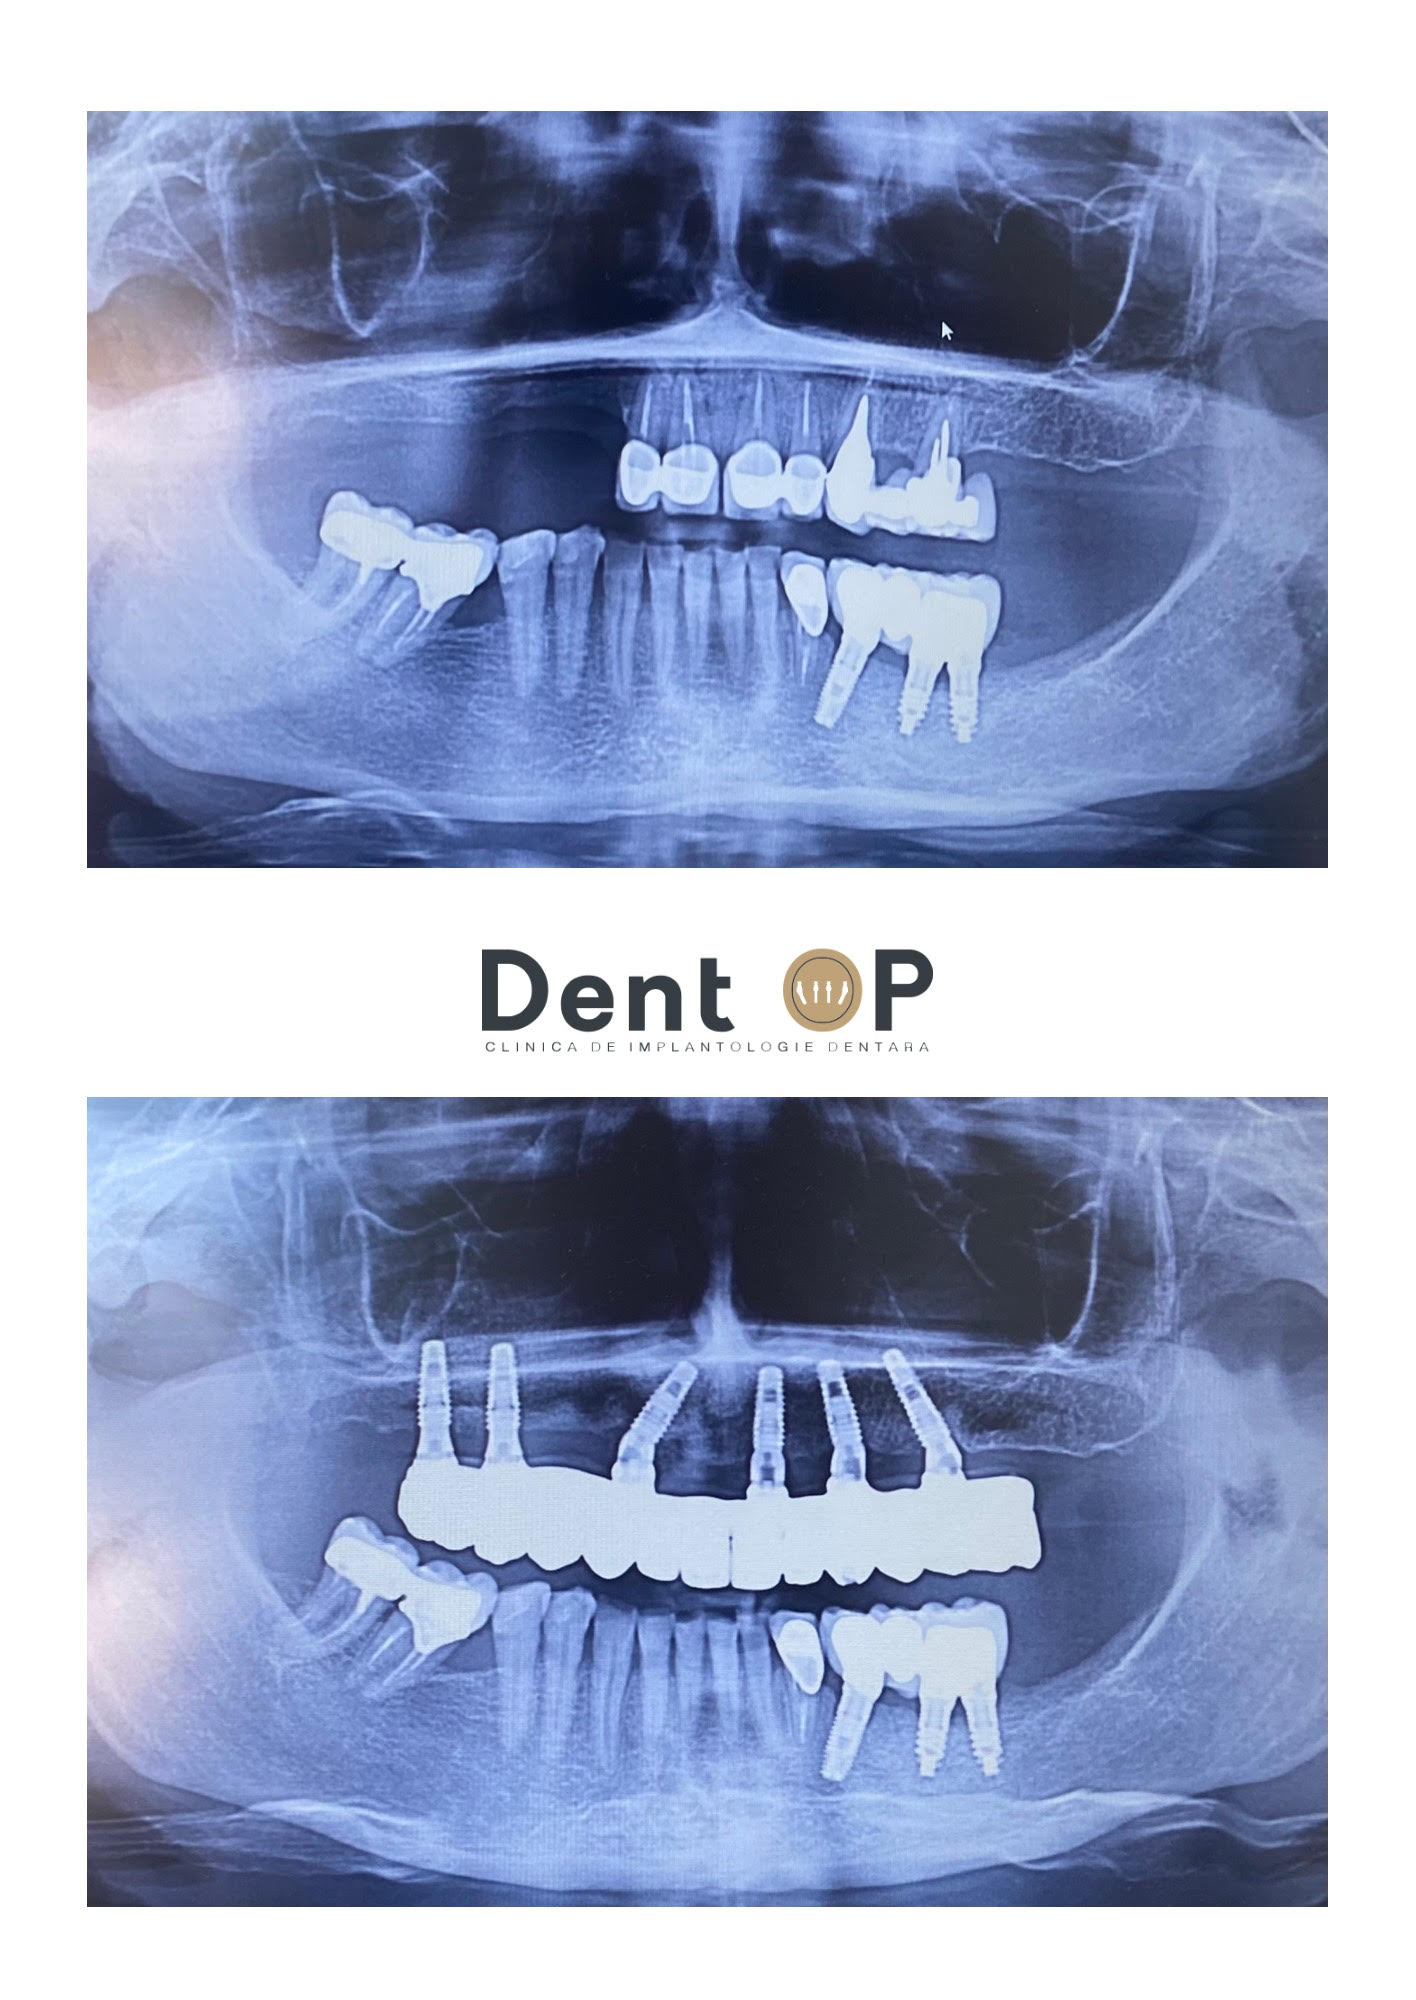

În radiografiile de mai jos se poate observa starea implanturilor dentare înainte și după intervenția ,,Dantură Fixă în 24h pe implanturi dentare” la clinica de implantologie DentOP.